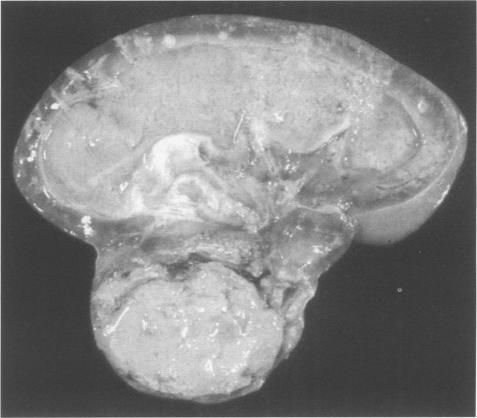

A 9-year-old, quarter horse gelding with obstructive urethrolithiasis was treated with a perineal urethrostomy. The horse's condition deteriorated and abdominocentesis confirmed septic uroperitonitis. The horse was euthanized and postmortem examination revealed peritonitis, a tear in the lateral wall of the bladder, and a nephrolith within the left renal pelvis.

一匹9岁的夸特马种公马患有阻塞性尿道结石,接受了会阴尿道造口术治疗。该马的病情恶化,腹腔穿刺证实为感染性尿性腹膜炎。对该马实施了安乐死,尸检发现有腹膜炎、膀胱侧壁撕裂以及左肾盂内有一枚肾结石。